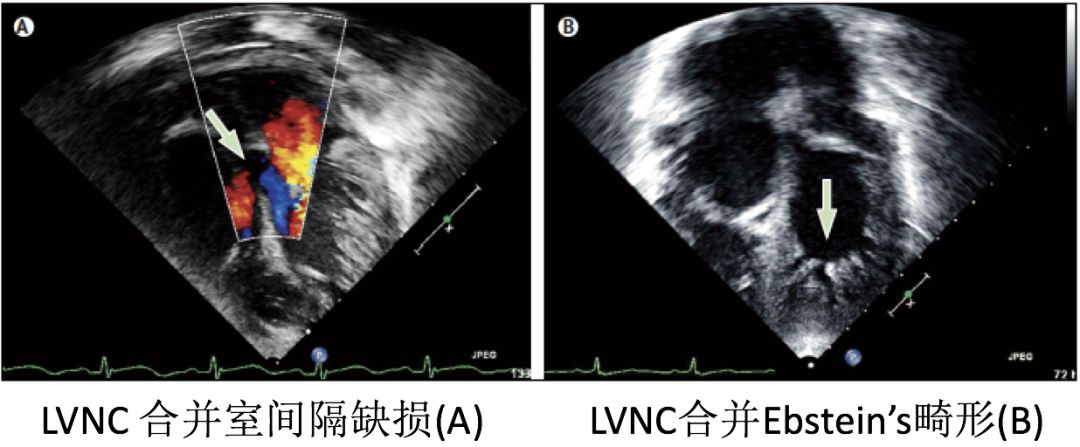

• 根据其临床表现,又分为8种亚型,分别为:1.Benign LVNC,2.LVNC with arrhythmias,3.Dilated LVNC,4.Hypertrophic LVNC,5.Hypertrophic dilated LVNC,6.Restrictive LVNC,7.Right ventricular or biventricular LVNC,8.LVNC with congenital heart disease

LVNC 的人群发病率为0.014%~0.3%,该疾病可孤立存在,或与其他先天性心脏畸形并存